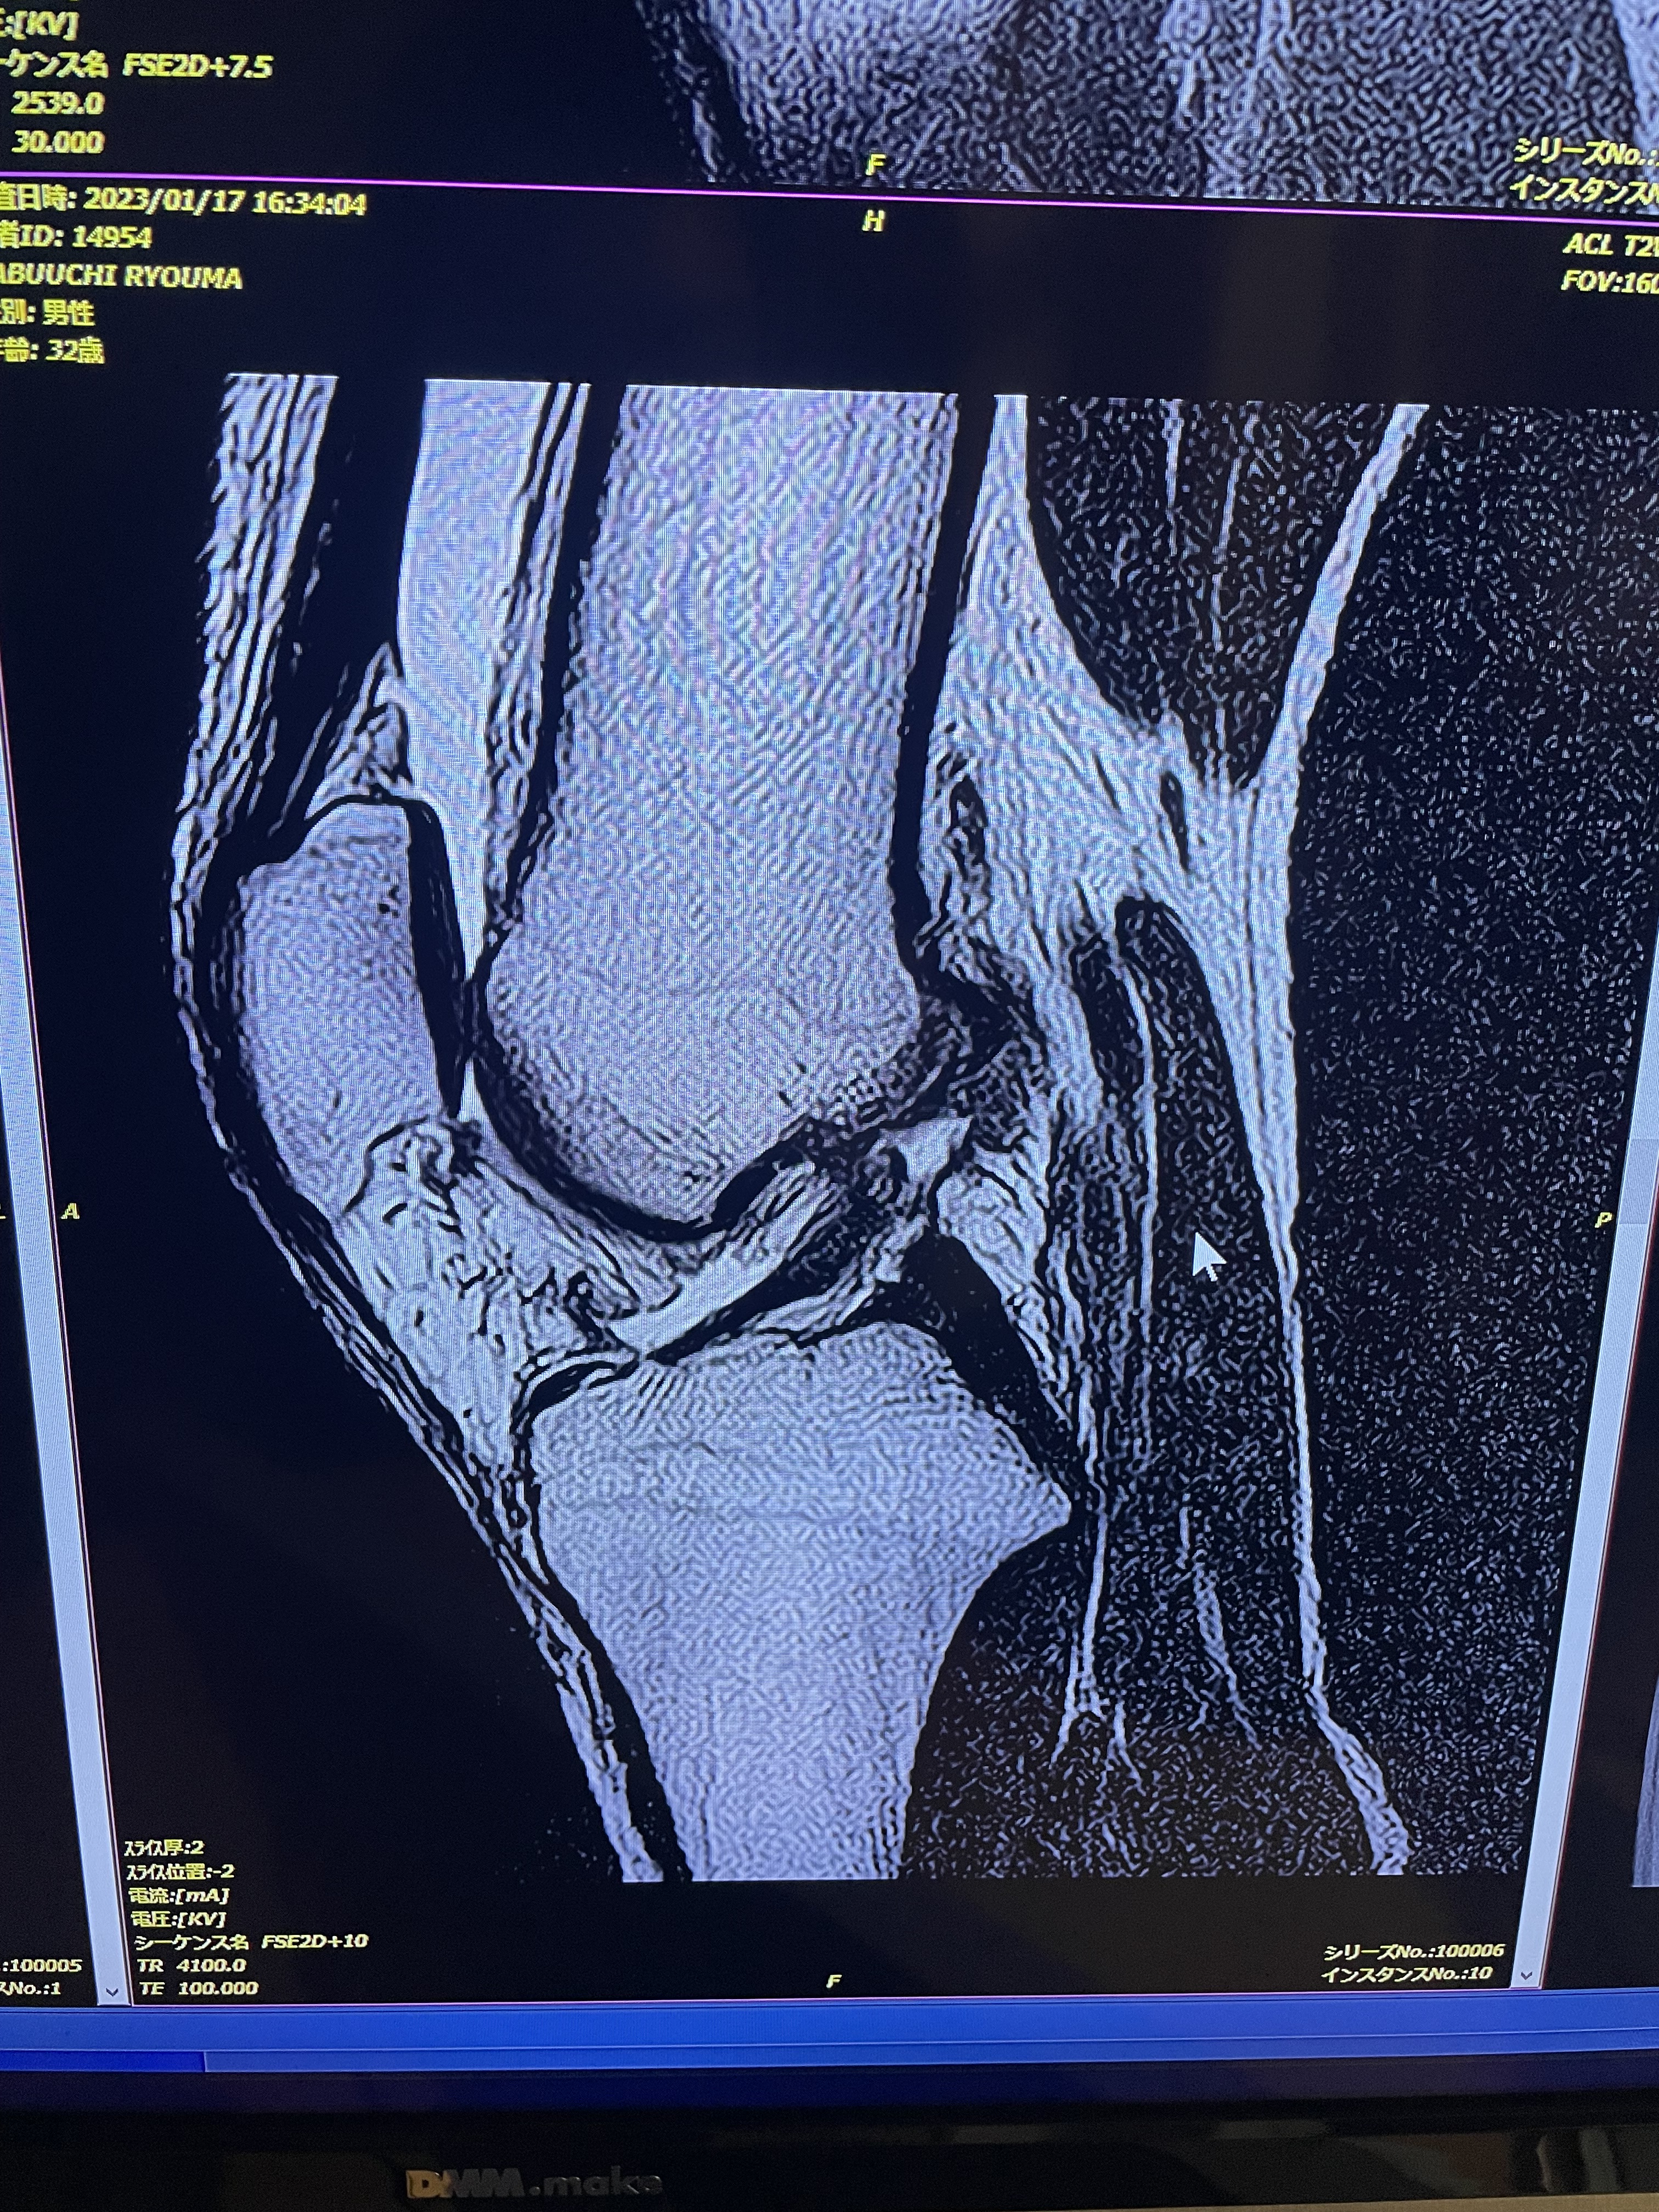

前十字靭帯断裂について

今日は前十字靭帯断裂について書こうと思います。

僕が今、断裂しているからです。

前十字靭帯断裂とはどのようなケガなのか??

前十字靭帯断裂の症状は受傷時は激しい痛みや「ブツッ」という断裂音を感じることがあります。また、靱帯からの出血により関節内に血液が溜まり、関節の腫れを伴います。受傷後は徐々に症状が改善し数週間で歩けるようになりますが、膝の不安定感や、膝が抜ける感じが生じることもあります。

僕は完全に断裂なので、手術療法をしないといけません。

ちなみに半月板も損傷しておりました…。